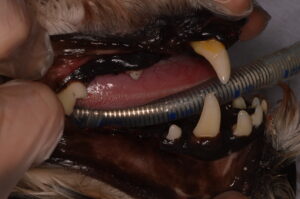

今回は、お口の排膿をきっかけに歯科処置を行ったワンちゃんの症例をご紹介します。

今回ご紹介するのは、ミニチュア・シュナウザーの女の子(9歳)です。

上顎の奥の歯ぐき付近にできものがあり、そこから膿が出ているということで来院されました。

歯ぐきからの排膿(内歯瘻)が確認されましたが、明らかな歯冠破折は認められませんでした。